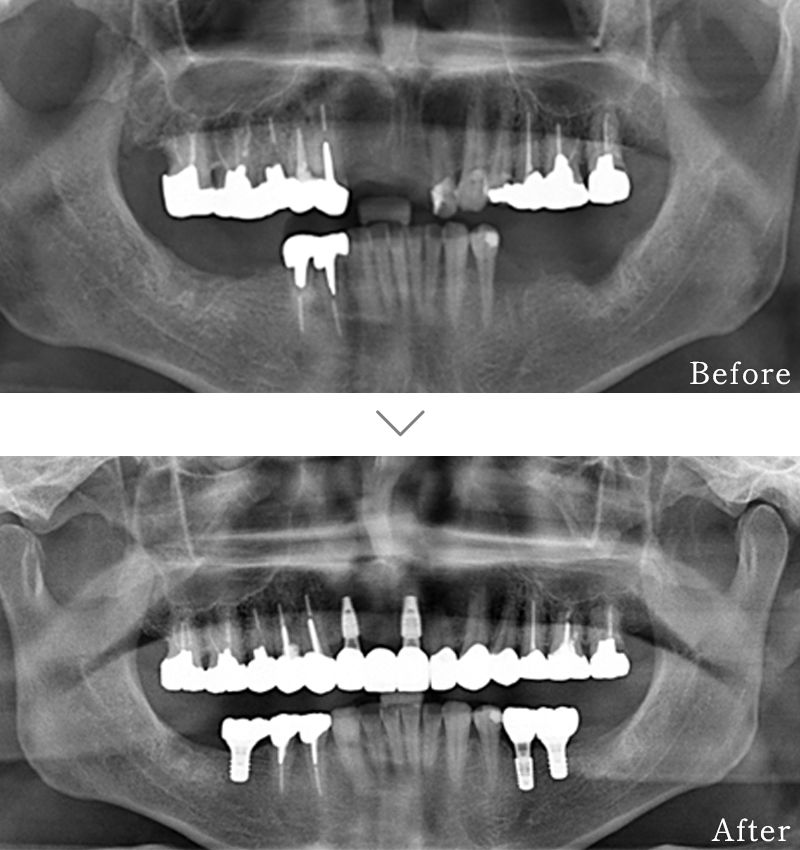

主訴 入れ歯も合わず、しっかりと噛んで食事ができないとのことで来院されました。

治療法 上下ともにALL-ON-6と呼ばれる最少本数のインプラントで全ての歯を回復する治療を行なっています。歯の部分は全てセラミックで作成されています。

治療期間 5ヶ月

費用 CT:16,500円(税込)

+ 静脈内鎮静法:66,000円(税込)

+ ALL-ON-6×2:5,500,000円(税込)

合計:5,582,500円(税込)